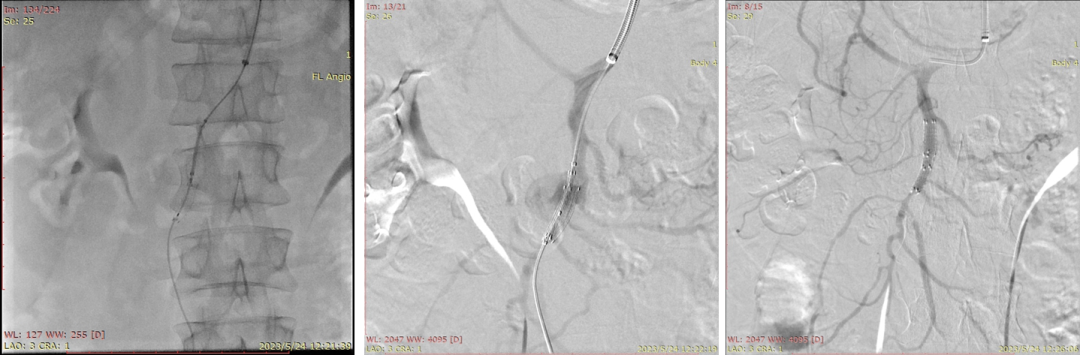

20230524DSA:VB支架植入

20230530CTA(术后1周):夹层动脉瘤隔绝完全